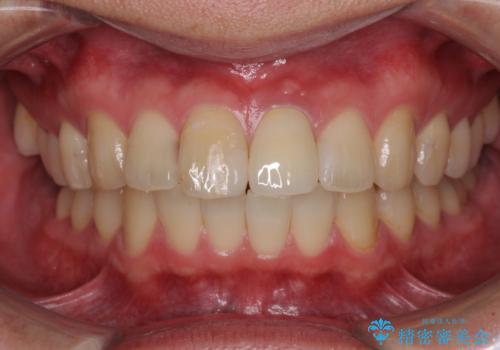

前歯の変色が気になる オールセラミッククラウンによる審美歯科治療

- 前歯が変色してしまったとのことで来院された患者様です。

変色が気になっていたものの痛みがなかったので看過していましたが、歯肉が腫れることが頻回となったため来院されました。

歯髄は既に壊死していたため、根管治療を行い、その後オールセラミッククラウンにて補綴することとしました。

変色による周囲に視線が気にならなくなり、明るいくらいとなりました。